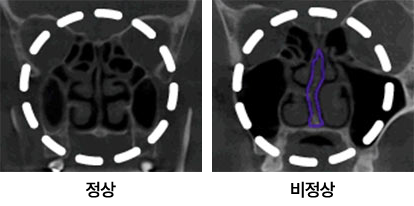

비중격 만곡증에 의한 비염

비염 진단방법

비염은 코막힘, 콧물, 재채기, 가려움증 중

하나 이상의 증상이 있는 질환으로

코가 막히면 진단을 통해 비염인지 확인하는 것이 중요합니다.